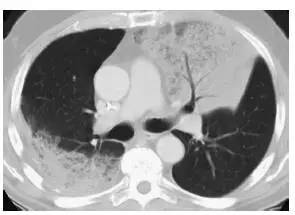

图7 弥漫性细支气管肺泡癌

A. 胸片显示右肺基底部的实变( 箭头);

B.5mm 层厚的CT 显示多个区域的实变,含有空气支气管征,多发的边界不清的结节,这些结节呈小叶中央分布,代表气腔或腺泡结节,在弥漫性细支气管肺泡癌中很常见